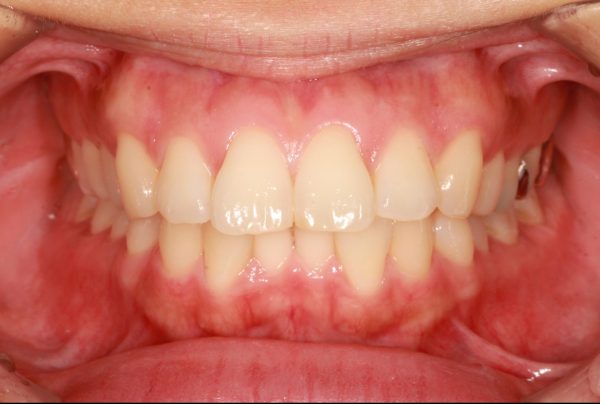

開咬状態は改善され、上下の歯がしっかりと噛み合いました

抜歯を行ったことで、上顎の前後的な距離が適正になりました。

ねじれ(翼状捻転)も治りました

同じように 下あごも前後的な距離が短くなり、適正な長さになりました。

上下の顎が適正な長さになった、この効果で上下の前歯が下がりました。

前歯、側方歯がしっかりと嚙み合いました